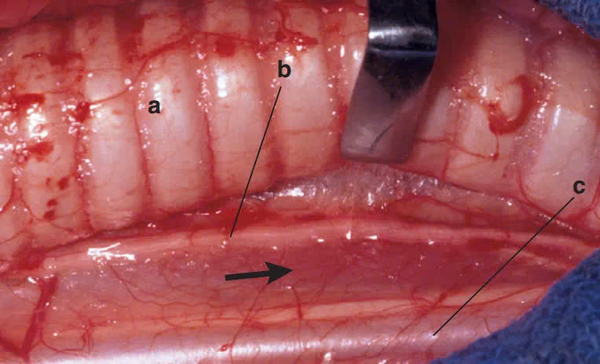

Hình ảnh cận cảnh cho thấy:

(a) Khí quản,

(b) Dây thần kinh quặt ngược thanh quản,

(c) Vỏ động mạch cảnh.

Đường tiếp cận được xác định bởi mũi tên đen, nằm giữa dây thần kinh quặt ngược thanh quản và vỏ động mạch cảnh.

Chúng ta cần đặc biệt lưu ý đến:

(a) Dây thần kinh quặt ngược thanh quản,

(b) Vỏ động mạch cảnh, nơi chứa động mạch cảnh cùng với thân thần kinh giao cảm, có màu trắng rõ ràng.

Những cấu trúc quan trọng này tuyệt đối không được tổn thương trong quá trình phẫu thuật, vì có thể gây ra biến chứng nghiêm trọng liên quan đến chức năng thần kinh và tuần hoàn.